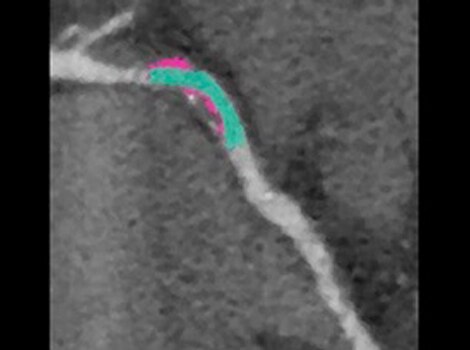

Cardiac MR

Excellent temporal and spatial resolution to assess lesion integrity.

Pre-Procedure Planning

If considering catheter ablation as a treatment option, pre-procedure planning can involve use of MR or CT imaging to identify anatomical targets for the procedure and understand the extent of AF. These images can help guide decisions on necessity of left atrial appendage closure in certain populations.3

CINE IR optimal TI value for MDE in a rapid, single breath-hold.